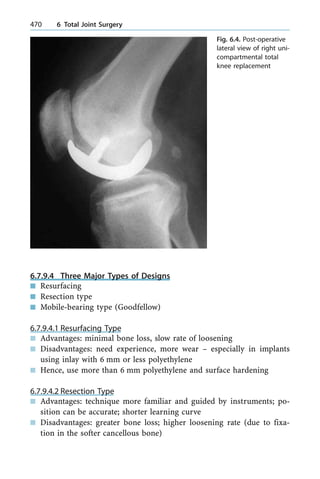

• 249.

n Open malletwith fracture and/or DP subluxation; methods to fix frac- ture vary from k-wire, tension-band, screw, etc. Even with anatomic fixation, splinting or trans k-wire may still be needed n Untreated natural Hx may sometimes develop swan-neck deformity, the reason being that if patient has lax ligaments, the combination of proximal migration of the extensor hood with increased extensor force at PIP and volar plate laxity causes the deformity n Stiffness and osteoarthritis (OA) of DIPJ to start with ± may need fu- sion n Chronic mallet but at less than 3 months ± closed treatment mostly n Chronic mallet and swan neck ± a more complex situation which needs oblique retinacular ligament reconstruction and superficalis te- nodesis 3.3.3.4.2 Zone 2 n Commonly associated with bony fracture, late tenolysis, and capsulot- omy may be needed n Complete open lacerations just repair (if untreated also causes mallet) n Partial cases especially if closed sometimes conservative, especially if no significant extensor lag and encourage early motion 3.3.3.4.3 Zone 3 n Central slip cut ± volar displacement of lateral band ± boutonniere de- formity may ensue ± Closed acute central slip ± extension splint and trans-articular k- wire ± Open repair ± may protect with transarticular k-wire for 6 weeks ± Associated fracture ± options include fixation versus excision of fragment and reattachment central slip ± Chronic rigid ± splint it straight (dynamic or serial static), then re- construct by scar excision, and reattach (ensure balance between lateral bands and the repaired central slip). Once balance was es- tablished between lateral bands and the repaired central slip, con- sider transarticular k-wire spanning the PIPJ, and mobilise the DIPJ and MCPJ. (More difficult are cases in which PIPJ cannot be splinted straight ± initial volar release to restore passive extension, then central-slip reconstruction) a 3.3 Tendon Injuries 231